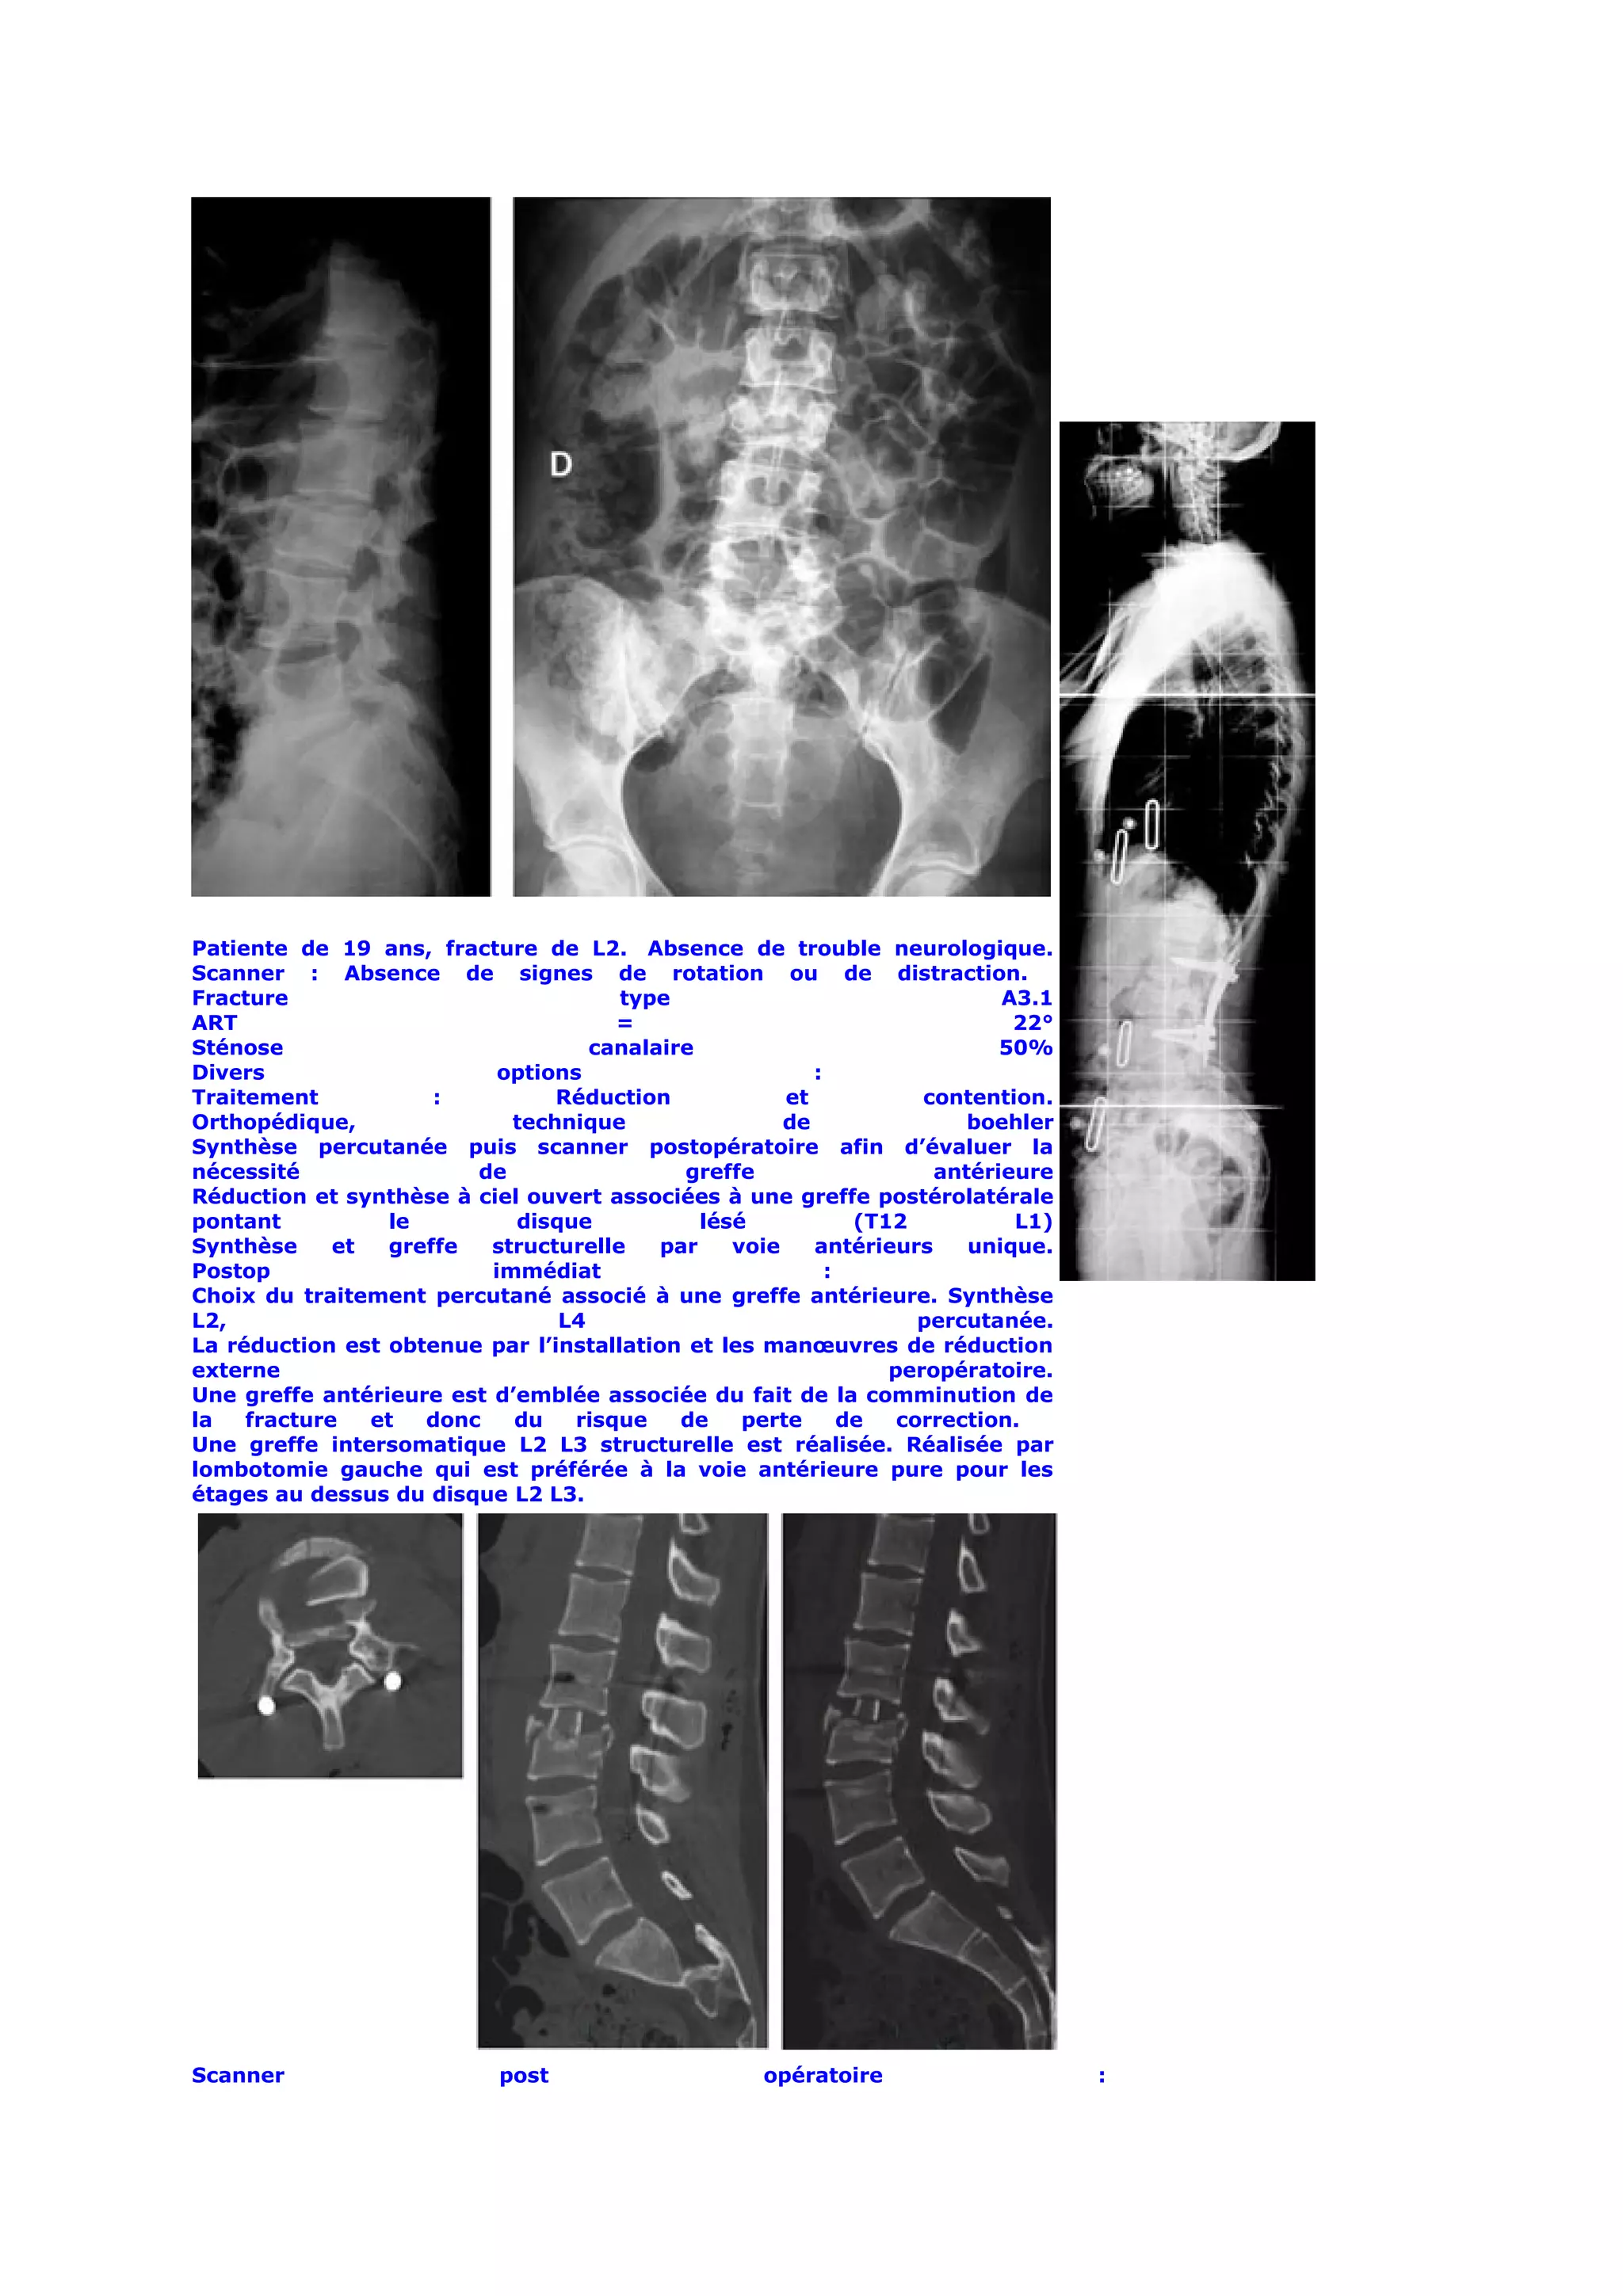

Patiente de 19 ans, fracture de L2. Absence de trouble neurologique.

Scanner : Absence de signes de rotation ou de distraction.

Fracture                              type                                 A3.1

ART                                   =                                     22°

Sténose                            canalaire                               50%

Divers                     options                       :

Traitement           :          Réduction             et            contention.

Orthopédique,               technique                 de                boehler

Synthèse percutanée puis scanner postopératoire afin d’évaluer la

nécessité               de                  greffe                   antérieure

Réduction et synthèse à ciel ouvert associées à une greffe postérolatérale

pontant          le         disque            lésé            (T12          L1)

Synthèse     et  greffe   structurelle    par    voie    antérieurs     unique.

Postop                    immédiat                         :

Choix du traitement percutané associé à une greffe antérieure. Synthèse

L2,                             L4                                  percutanée.

La réduction est obtenue par l’installation et les manœuvres de réduction

externe                                                          peropératoire.

Une greffe antérieure est d’emblée associée du fait de la comminution de

la   fracture   et  donc    du    risque   de     perte      de   correction.

Une greffe intersomatique L2 L3 structurelle est réalisée. Réalisée par

lombotomie gauche qui est préférée à la voie antérieure pure pour les

étages au dessus du disque L2 L3.

Scanner                     post                    opératoire                    :

Restitution          de           la           courbure            physiologique.

Une fois la fusion L2 L3 obtenue, la synthèse pourra être retirée pour libérer l’étage L3 L4

indemne de lésion.